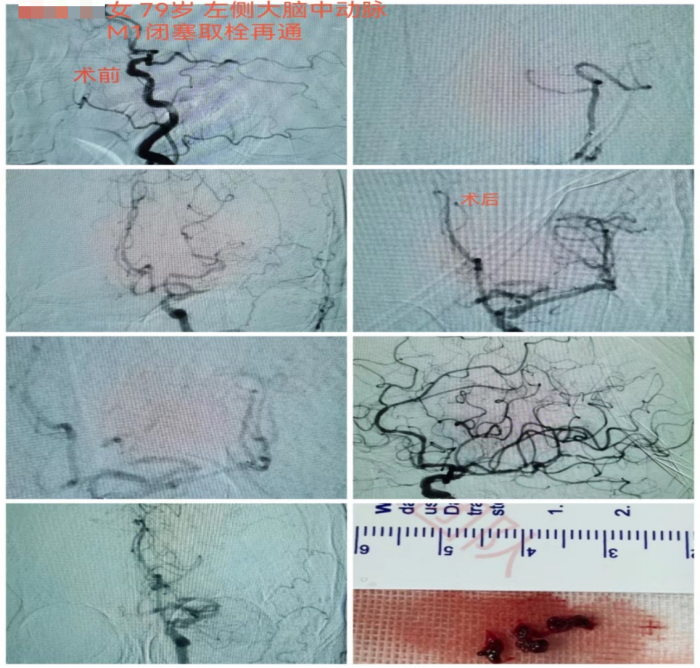

9时左右,家属将蒋奶奶送至长沙市融城医院,行头部CT和MRI后考虑左侧大脑中动脉闭塞引起的脑梗死,需立即接受动脉取栓治疗。长沙市融城医院立即联动91短视频

12时24分,“120”救护车到达91短视频

(南华大学附属长沙中心医院)急诊,立即完善头颅CTA提示左侧大脑中动脉M1段栓塞。监测生命体征以及复查必要检查项目后,神经内科副主任医师冯铁桥与患者家属沟通病情及手术相关事项,签字后患者被转入早已做好准备的介入导管室,行“左侧大脑中动脉闭塞急诊介入开通术”,施行动脉取栓。

12时45分,患者被推进介入导管室,此时患者仍处于颅内大血管闭塞动脉取栓的黄金时间窗内(6小时),救治工作紧张有序地展开。10分钟后股动脉穿刺成功,患者的取栓血管通路顺利建立。

13时33分,患者闭塞的血管被开通,缺血的脑组织恢复有效的血流灌注。术后,患者血管再通良好,闭塞远端血流较前明显改善。患者右侧肢体肌力明显较发病时好转,能简单发声、听懂对话。

第二天,患者能自行下地行走,语言功能也得到恢复。从卒中发病到完成介入取栓治疗,蒋奶奶的“生死时速”过程历经6小时40分钟。